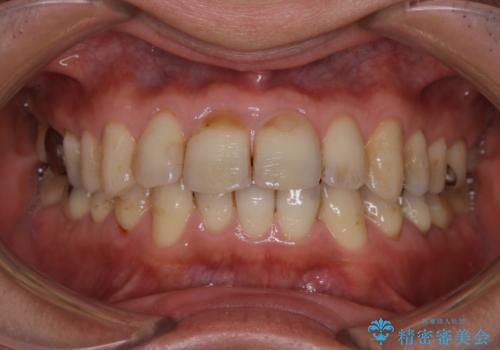

- 歯科がかなり久しぶりで、今後虫歯治療予定のためまずはクリーニングを希望されました。PMTC60分コースを行いました。

歯の表面に、茶色く色が残っている所がありますが、これは詰め物の変色の所と、虫歯になっている所です。以前に、CR(コンポジットレジン)による虫歯治療がされています。

CRは経年的劣化や、着色してしまうことがあります。PMTCでクリーニングを行うと、古いCRが目立つことがあるため、気になる際は詰め替えを行います。

茶色くなっている部分が、着色なのか、劣化なのか、虫歯によるものなのかは判別が難しいことがあります。そのため、定期的にPMTCを行うことで状態の確認が的確に行えます。

また、治療が開始される前などにも、全体的にクリーニングを行いご自身本来の歯の色、状態を精密に確認することが大切です。